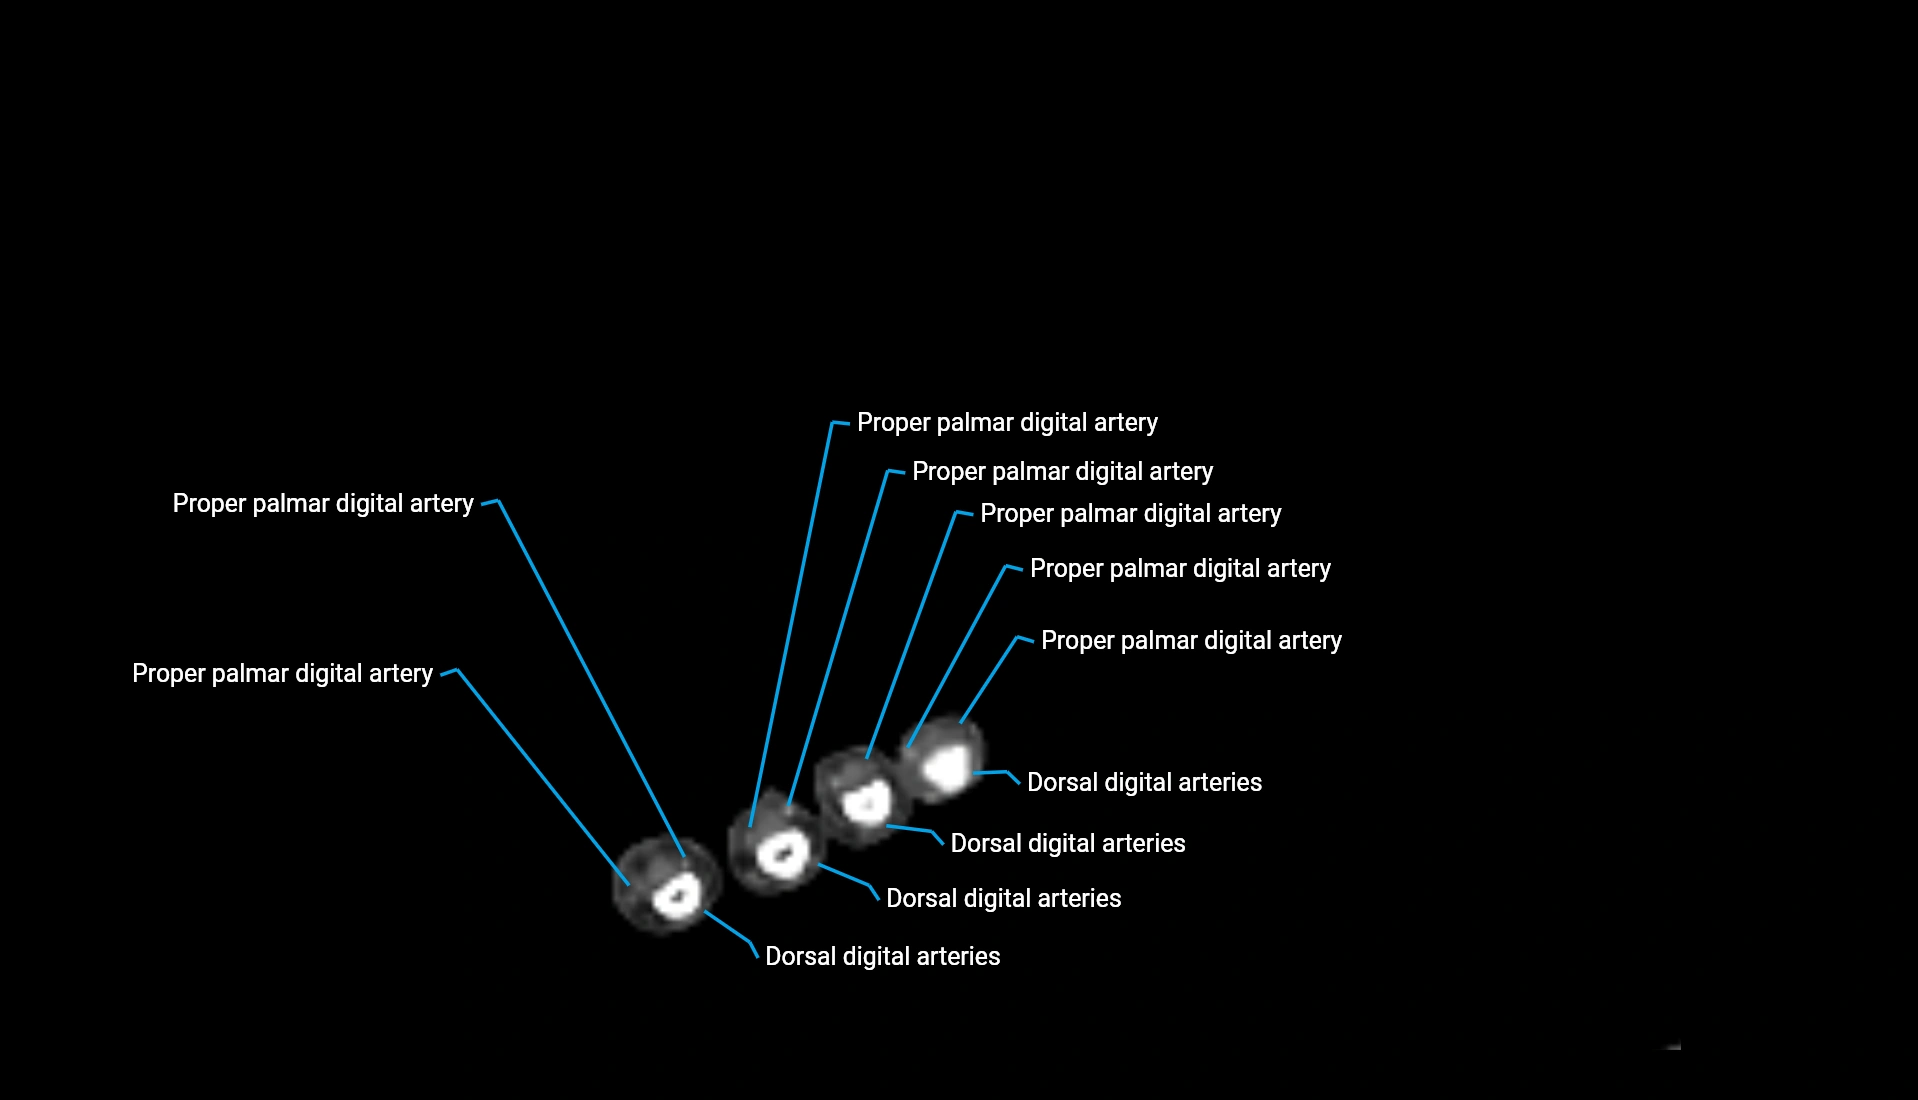

CT Appearance

Non-Contrast CT:

• Cortex: High-density, sharply defined

• Subchondral bone: Dense cancellous matrix

• Articular surface: Smooth concave contour articulating with the capitellum

• Excellent for evaluating bone integrity, alignment, and subtle fractures